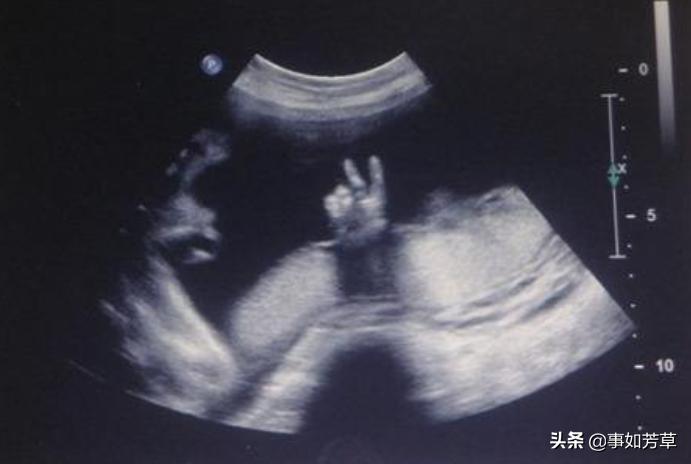

有不少宝妈其实很害怕胎儿在肚子里胎动,有时候会突然疼一下,就怀疑胎儿是不是在肚子里用指甲抓妈妈,其实胎儿在羊水中的时候指甲是软软的,根本不具备任何"*伤杀**力",而且胎儿几乎一直保持着握拳的姿态,更不可能到处乱抓了。